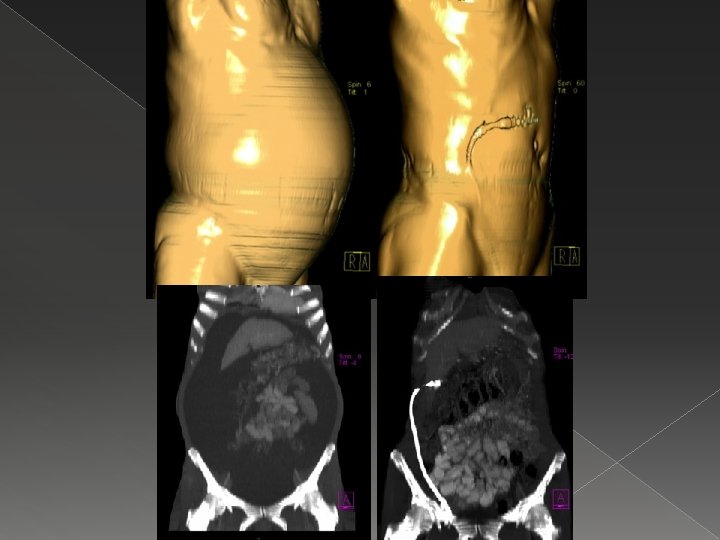

Peritoneovenöz şant � Hem malign hem benign sirotik refrakter asitte ve plevral efüzyonda alternatif yöntem. � Şant oklüzyonu, enfeksiyon, koagülopati (DİC), derin ven trombozu, sıvı yüklenmesi, hava embolisi ve tümör hücrelerinin disseminasyonu önemli komplikasyonlarıdır. � Malign hücre negatif olan hastalarda şant daha iyi ve uzun süre çalışır.

Peritoneovenöz şant Denver Ascites Shunt